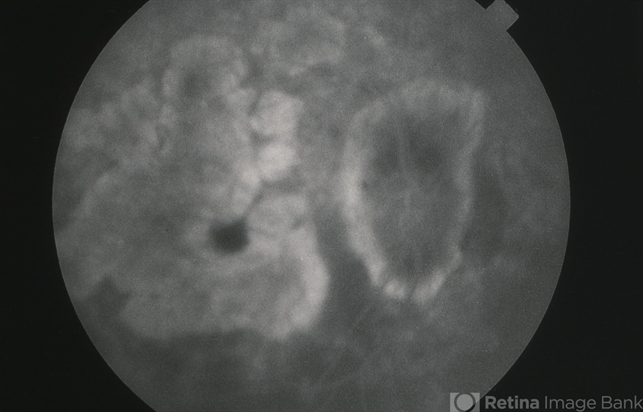

- CHORIOCAPILLARIS ATROPHY

- fluorescein angiogram (FA), FA late phase, hereditary choroidal dystrophy, hereditary choroidal atrophy

- Late-phase fluorescein angiogram image of the right eye of a 64-year-old white male with central areolar choriocapillaris atrophy showing late leakage from intact choriocapillaris around the perimeter of the disc and macular areas of choriocapillaris atrophy; VA= 20/50